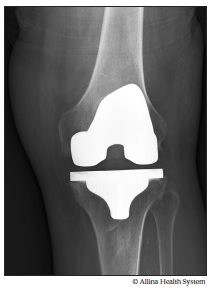

Xray total knee replacement

An X-ray shows the artificial joint (prosthesis) after a knee replacement.